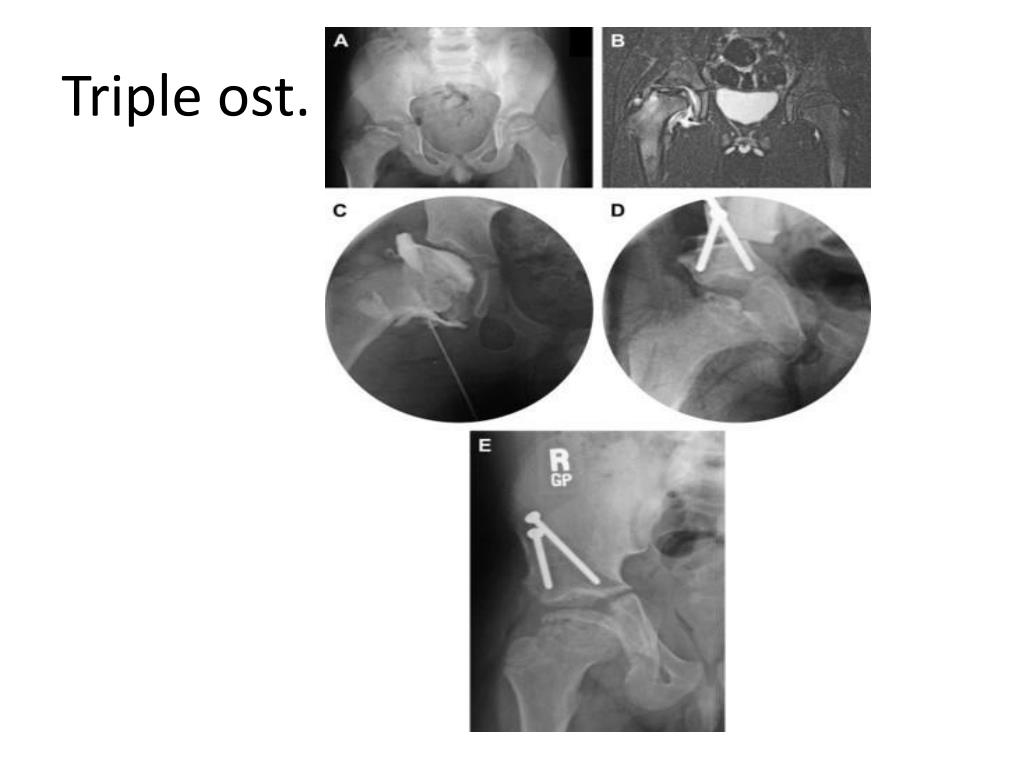

26. Triple pelvic osteotomy

27. Triple ost.